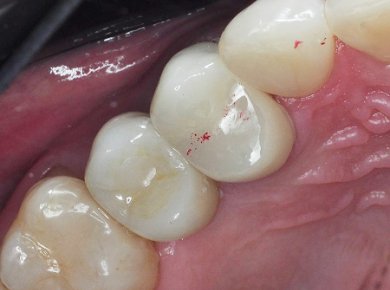

После завершения эндодонтического лечения и стабилизации состояния зуба врач-ортопед провёл подготовку зуба под протезирование. Изготовлена и зафиксирована коронка. (Фото 2 и 3).

Результат: Болевые ощущения при накусывании полностью устранены, дискомфорт при жевании отсутствует. Зуб сохранён и полноценно восстановлен. После установки керамической коронки восстановлены анатомическая форма и жевательная функция.